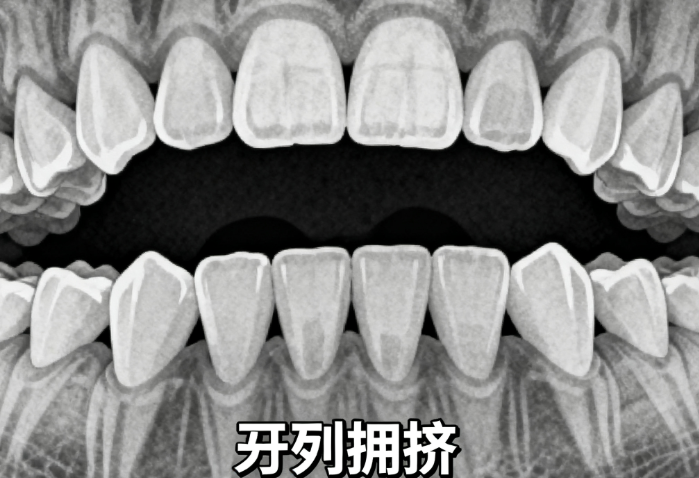

4. 矯正一定要拔牙嗎?

并非所有正畸病例都需要拔牙。是否需要拔牙取決于牙齒擁擠程度、頜骨發(fā)育情況等多方面因素。張寧醫(yī)生會通過全方面檢查評估,制定較保守且有效的治療方案。